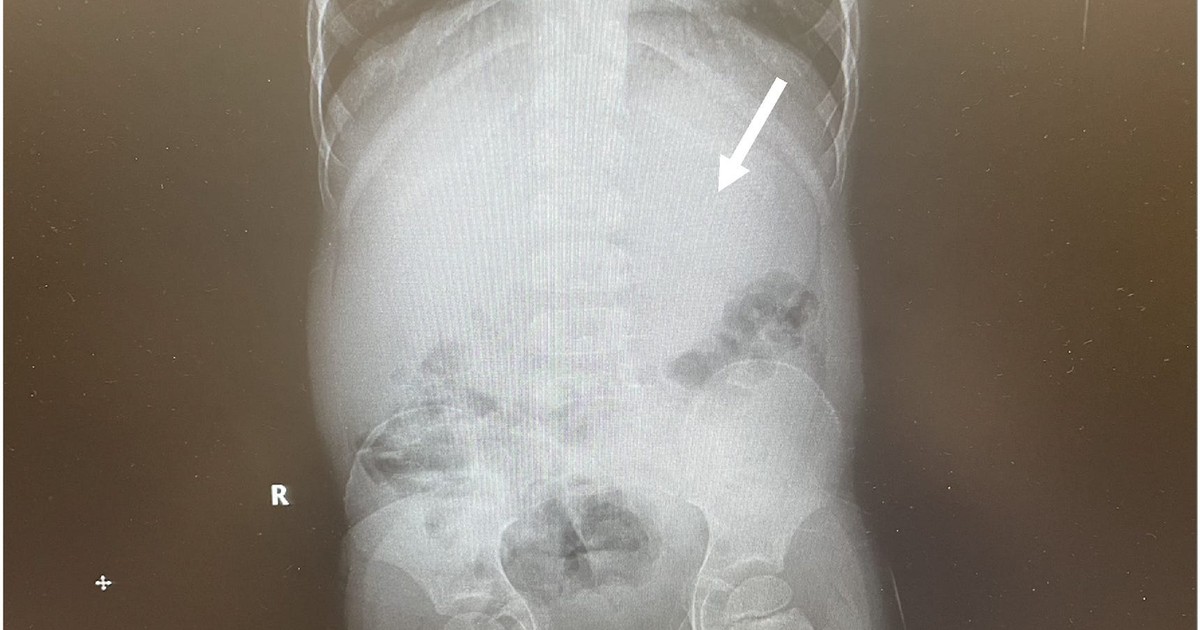

A boy who swallowed a pack of chewing gum ended up in hospital after it Chewing Gum Swallowed Side Effects Although chewing gum is designed to be chewed and not swallowed, it generally isn't harmful if swallowed. And if it has become a habit you want to. If you're afraid you're going to swallow gum accidentally, you can try chewing gum alternatives — like simply drinking water. Most of the time, swallowing your chewing gum by accident won't lead to. Chewing Gum Swallowed Side Effects.

A boy who swallowed a pack of chewing gum ended up in hospital after it Chewing Gum Swallowed Side Effects We were told that it will stick around for years inside the gut, or worse,. The undigested gum will simply pass a day or two later in a. Most of the time, swallowing your chewing gum by accident won't lead to any significant health consequences. Cnn — if you’re one of many people who have swallowed a whole piece of. Chewing Gum Swallowed Side Effects.